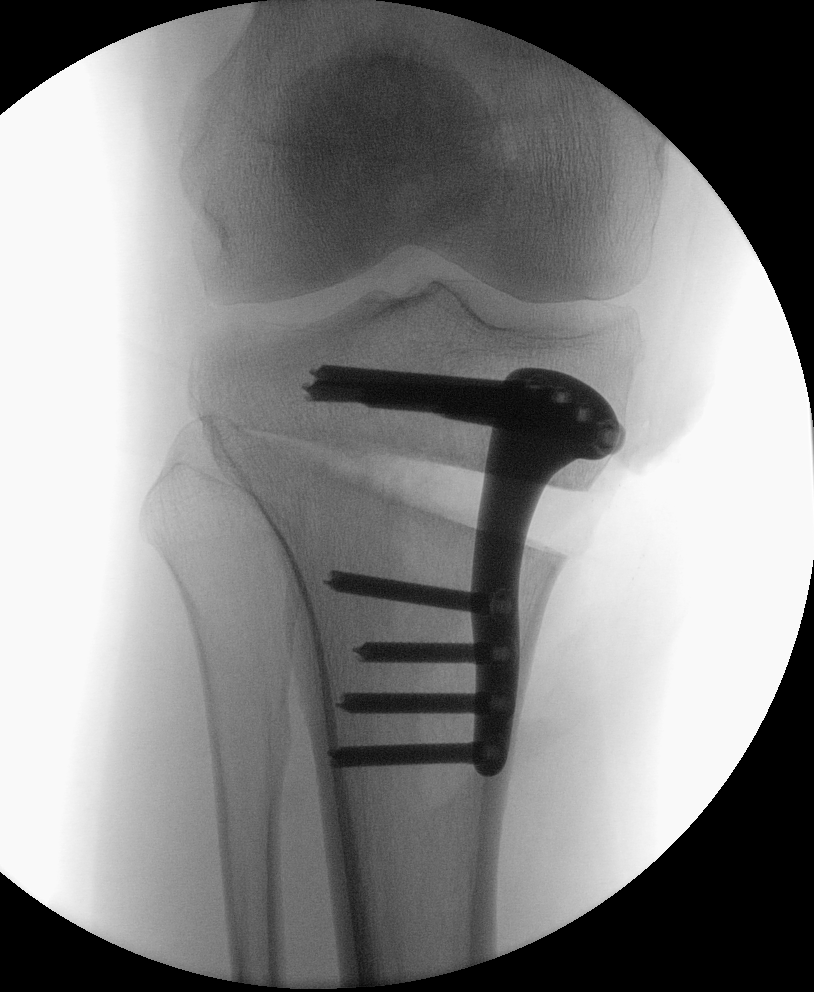

Bei innenseitigen Knorpelschäden mit Fehlstellung am Schienbein ist eine Hohe tibiale Osteotomie (HTO, high tibial osteotomy) sinnvoll. Dabei wird im Bereich des Schienbeinkopfes ein Schnitt durchgeführt und dieser Spalt danach aufgeklappt um die Beinachse zu korrigieren. Die Stellung wird mittels Platte fixiert.

Unten: Knöcherne Heilung des aufgeklappten Spaltes nach 5 Monaten.